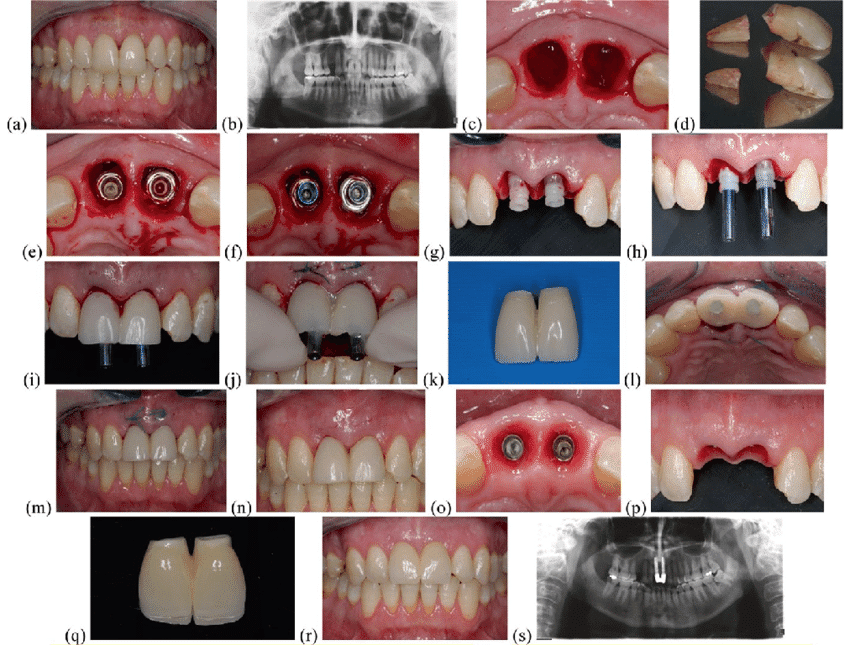

زراعة الأسنان الفورية قبل وبعد بالصور